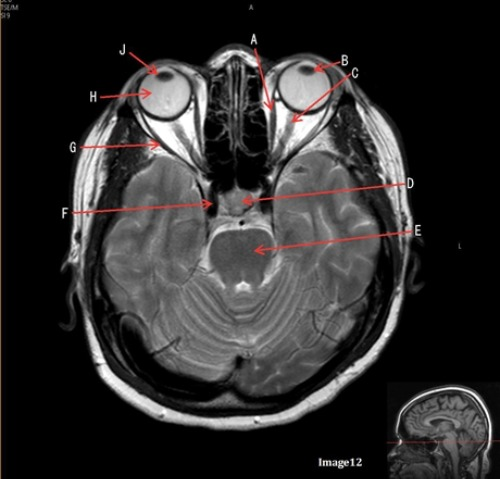

Letter G in Image 12 is pointing to:

B. Lateral rectus muscle

Letter C in image 12 is pointing to:

A. Left optic nerve

Letter D in Image 12 is pointing to:

B. Pituitary gland

Letter E in Image 12 is pointing to:

D. Pons

Letter A in image 12 is pointing to:

C. Medial rectus muscle

Letter H in Image 12 is pointing to:

E. Globe

Letter B in Image 12 is pointing to:

D. Lens

Letter J in Image 12 is pointing to:

D. Right lens

Letter F in Image 12 is pointing to:

D. Internal Carotid artery